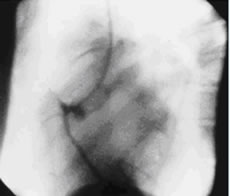

ソーンズ先生はクリーブランドクリニックの循環器内科医です。世界で初めて、選択的冠動脈造影を行い、冠動脈造影法を世界に広めたことで有名です。実はこの冠動脈造影をソーンズ先生が始めたのも「serendipity」なのです。またか!です。1958年10月、ソーンズ先生が大動脈造影を行おうと大動脈に留置した(と思った)カテーテルが、誤って冠動脈に入ってしまったのです。冠動脈に入っていたことに気づかずに造影剤を注入して得られたのが下の図2で、世界で最初に撮られた選択的冠動脈造影の画像です。

図2:世界で初めての冠動脈造影写真

この出来事が起きるまで、造影剤を冠動脈に注入することは禁忌とされていました。なぜかと言うと、造影剤を冠動脈に流すことは「一時的に冠動脈に血液が流れなくなること」を意味します。一時的にでも冠動脈に血液が流れなくなると、心臓は停止すると思われていたのです。しかし、ソーンズ先生が行った造影で心臓は一瞬、止まっただけでした。